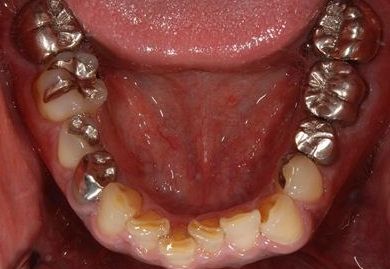

インプラントの症例写真 IMPLANT

インプラント治療+セラミック治療+歯肉歯槽骨整形術

| 治療内容 | インプラント2本、メタルボンドセラミッククラウン9本(メタルボンド用土台6本)、ハイブリッドセラミッククラウン2本(セラミック用土台2本)、ハイブリッドセラミックインレー5本、歯肉歯槽骨整形術 | ||||||||||||||||||||||||||||||||